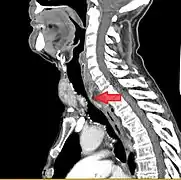

Rétrécissement trachéal (flèche rouge). Tomodensitométrie (coupe transversale).

Même tumeur (coupe sagittale).